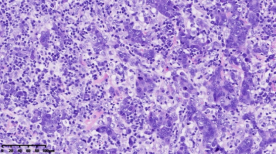

在本项研究中����,研究人员利用基本的组织形态学方法及免疫组织化学法对TNBC进行分型��:腔面雄激素受体型(LAR)(图1A)��,免疫调节型(IM)(图1B)�����,基底样免疫抑制型(BLIS)(图1C)���,间充质型(MES)(图1D)�����。评价各亚型临床病理参数(如发病年龄��、肿物大小���、淋巴结转移等)���,组织形态学(肿物中央瘢痕形成���、浸润模式����、肿瘤间质浸润淋巴细胞���、细胞排列方式���、细胞核形态��、核分裂计数���、间叶化生等)以及免疫表型(p53����、Rb���、PD-L1���、MMR等)�����,结果显示���:1.TNBC分型的临床病理����、组织形态学和免疫表型特征不尽相同���,有望成为复杂的基因表达谱分析的替代选择����,为TNBC的分型治疗及靶向治疗提供理论依据��;2.生物标记物 PD-L1作为重要的生物学指标�����,对个体化治疗及免疫治疗有重要的临床指导价值��;3.乳腺癌中dMMR作为一个低频发生事件��,不太可能作为免疫治疗有效性的评估手段����。该成果发表在Virchows Archiv期刊����,题目为“Subclassifying Triple-Negative Breast Cancers and Its Potential Clinical Utility”��。文章DOI为����:10.1007/s00428-022-03329-0�����。

图1. 基于组织形态学及免疫组织化学标记物的TNBC分型